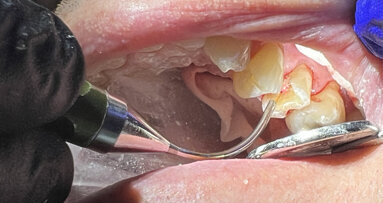

Pulpal exposures are unfortunately a routine occurrence when treating carious teeth and frequently lead to endodontic treatment owing to the size of the ...